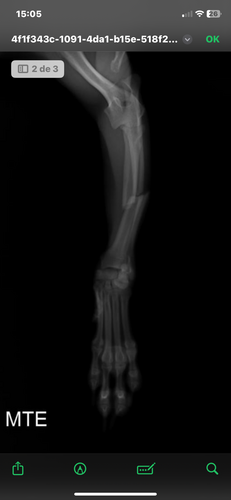

Oi, pessoal! Meu nome é Helen e esse é o Chico, meu pinscher cheio de energia, carinho e amor. Ele é parte da família, sempre alegre e protetor, mas infelizmente sofreu um acidente e fraturou o bracinho (membro torácico esquerdo).

Levamos o Chico ao veterinário e, após os exames e radiografias, o diagnóstico foi uma fratura deslocada que precisa de cirurgia com placa e parafusos. O procedimento é essencial para que ele volte a andar e brincar sem dor.